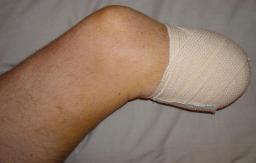

Preoperative (15th) images of left ankle

The following photos were taken 5 days before the amputation of Liam's left leg (below the knee). Liam has surrounded himself with a great team

which has allowed him to focus on work and not on the stress of the upcoming surgery. Of course leading that team is Madeline (Liam's wife). Madeline’s

dedication and support has been unwavering and the cornerstone of Liam’s strength. Note: The images shown were taken with Liam’s new 12.1 meg

digital camera following the CCD failure of Liam’s 5 meg camera.

Postoperative (15th) images of left ankle

On May 30th 2007 exactly 2 years and 2 days from the day that Liam had his skydiving accident, doctor Ott removed the lower part of Liam’s left

leg using what is described as an Ertl procedure. The Ertl procedure results in a residual limb that is stronger and has a greater ability to load bear.

It is expected that Liam’s fatigue will be greatly reduced as a result of the Ertl procedure. The X-Rays show the best details associated with the Ertl

procedure. It can clearly be seen that a piece of bone (from the fibula) has been used to bridge the gap between tibia and fibula. What can not be seen

is the amount of tissue and muscle that was used (found normally in the lower part of the limb) to form a sort of pocket surrounding the remaining bone.

Through the great efforts of doctor Ott and Owen from the Artificial Limb Specialist Group, Liam has been given good responses regarding his rate of

healing and his prognosis for a great recovering. At this stage Liam is using sleeves that help reduce swelling and shape the stump so that it best fits the

prosthetic limb that will be used by Liam to walk.